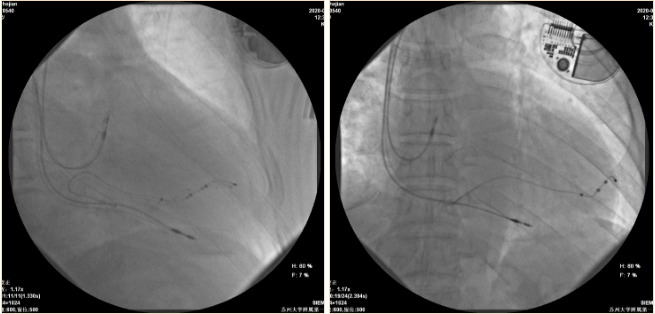

经左侧锁骨下静脉分别放置右房、右室主动固定起搏导线于右房心耳处及右室心尖部,参数满意;左室四极电极导线经冠状窦放置于后侧静脉,其中1、3两点参数满意,无膈神经刺激。

影像下起搏导线最终位置